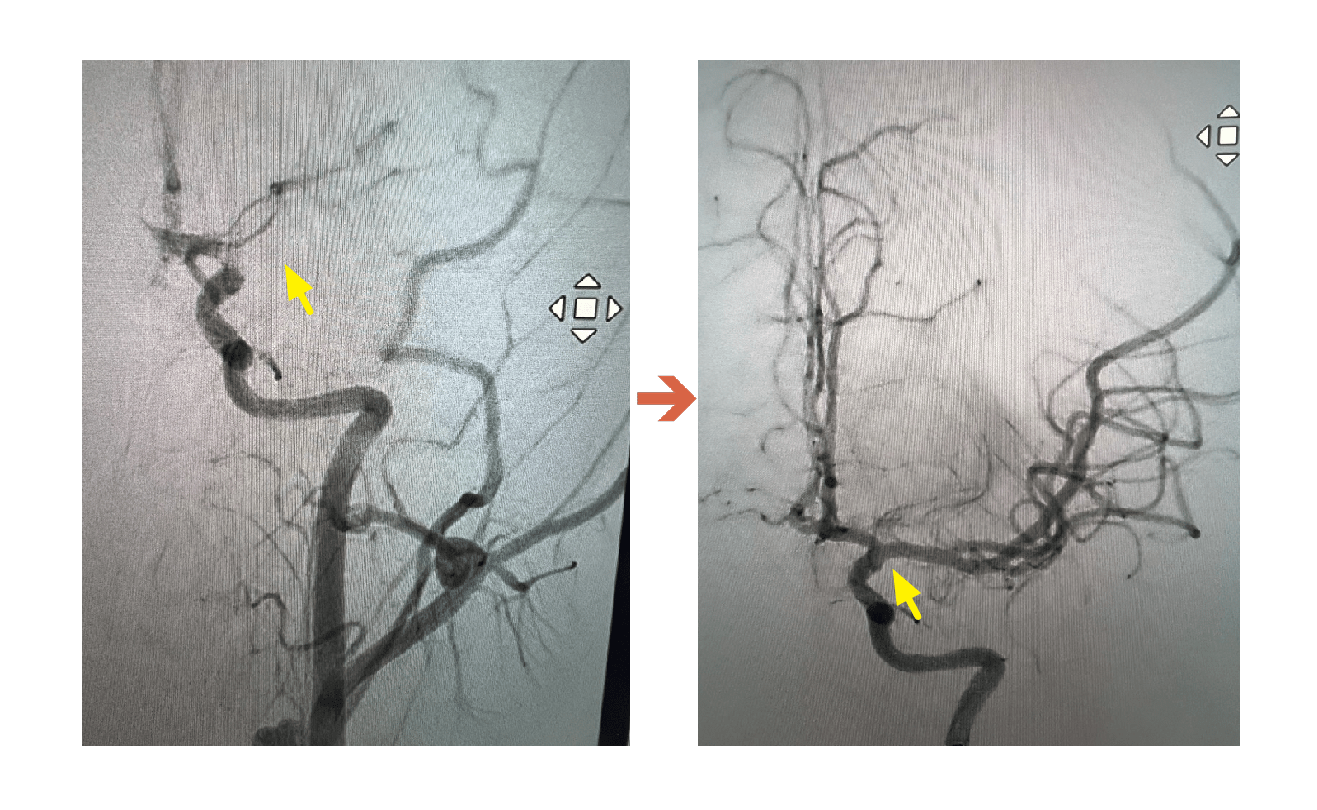

聯新國際醫院表示,該名學生被送往該院急診,影像檢查結果出爐後,神經內科醫師李振華迅速判讀,確定為左側中大腦動脈栓塞造成缺血性腦中風。在與家屬充分溝通後,影像醫學科主任暨取栓醫師郭葉璘隨即與取栓團隊進行急性腦中風顱內動脈血栓移除(Intra-arterial thrombectomy, IAT),並從腹股溝導引導管至左側中大腦動脈阻塞處,採用強力抽吸方式清除血栓。手術從開始到打通血管僅約10分鐘,成功取出4個血栓,最大達1.1公分。術後患者血流恢復暢通。

郭葉璘說明,左側大腦掌管語言中樞、身體右側活動能力及視覺與空間感知區域,中大腦動脈是負責供應大腦三分之二的重要血流。磁振造影中的擴散權重影像序列(DWI),能在中風發生後30分鐘內偵測腦部受損區域。檢查顯示該學生的左側中大腦動脈完全阻塞,磁振中的擴散權重影像序列也出現一塊淡淡的受損區域,這表示阻塞的危險性正快速提高中。若不即時處理,這片受損區域會持續擴大,腦部將因血栓壓迫而腫脹,同時往下壓迫腦幹,危及呼吸與心跳中樞,甚至造成生命危險。